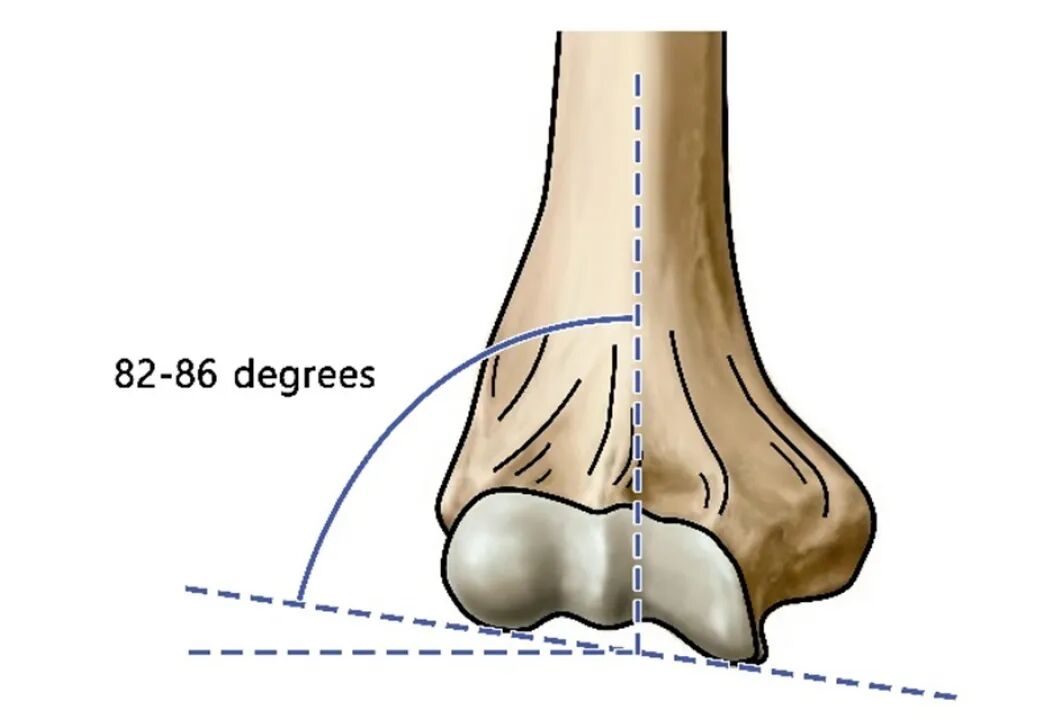

内翻畸形的测量

测量内翻畸形的方法多种多样;采用肱骨-肘-腕角humeral-elbow-wrist angle,这是Oppenheim等人提出的,最接近实际携带角(carrying angle CA)。该角度是在肘关节完全伸展、前臂外旋的状态下,通过普通X光片测量的。内翻角用负号(-)表示,外翻角用正号(+)表示。

肱骨-肘-腕角,定义为肱骨干线与前臂线的交角。